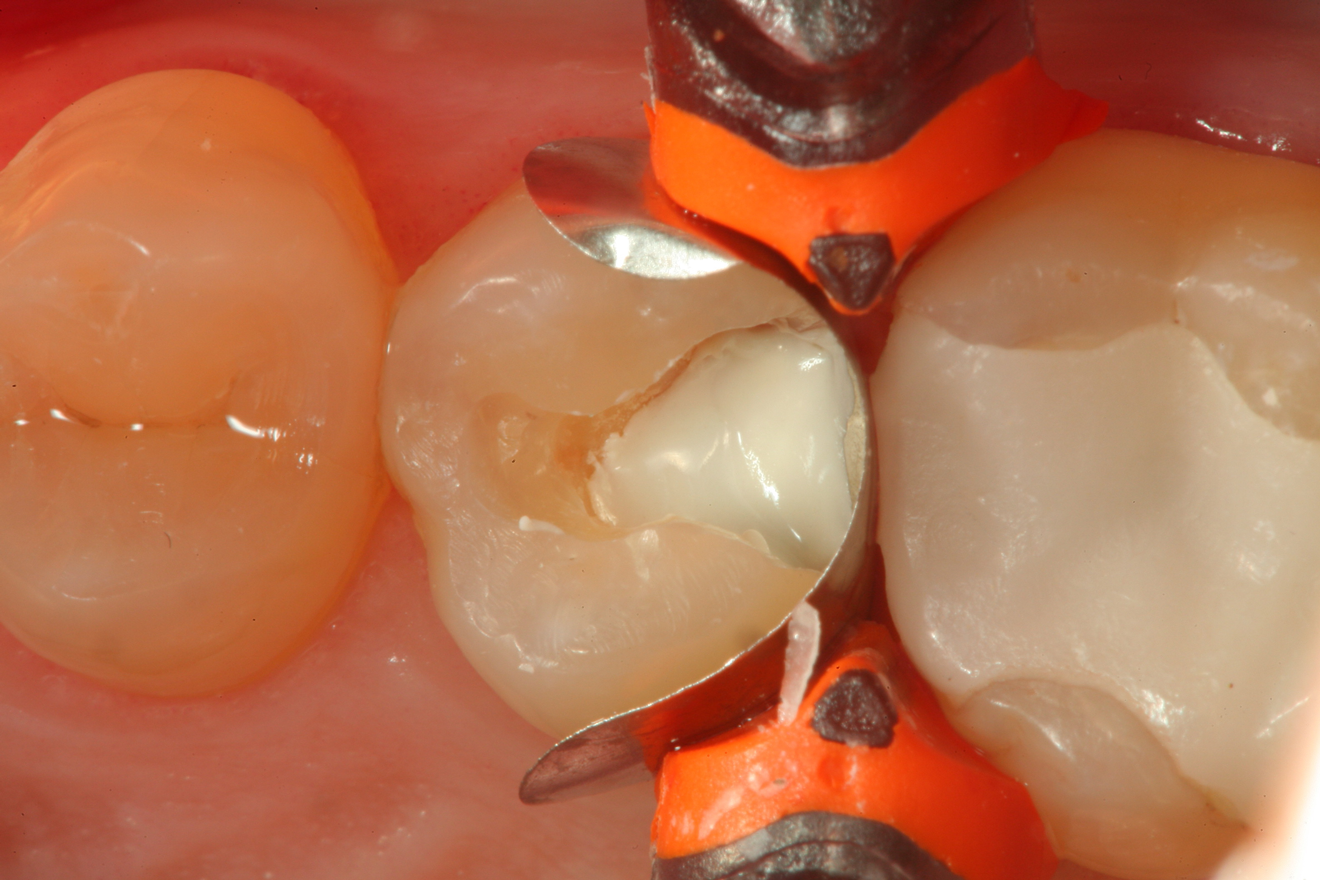

Fig 11. After removal of the existing restorations and associated recurrent decay, both cavities are very deep and there is a pinpoint pulpal exposure on tooth No. 19.

Figure 11

A 32 year-old female patientpresented with old composite restorations in tooth Nos. 18 and 19 that exhibited marginal leakage with potential for recurrent decay (Figure 10).  After excavation, both teeth had deep decay beyond the extent of the restorative material, with tooth No. 19 having a "pinpoint" carious exposure of the pulp chamber (Figure 11).  Figure 12 is a diagrammatic representation of the therapeutics that were used after removal of infected dentin and control of the bleeding from the pulp exposure.  A pulp protectant/liner that is indicated for use on a direct pulp exposure (TheraCal LC, Bisco Dental Products) was placed directly on the exposed area and light cured.  Both preparations were then filled with a bioactive dentin replacement (TheraBase, Bisco Dental Products) to a point just apical to the dentoenamel junction (Figure 13).  Selective etch protocol was then used, etching the enamel (Select Etch HV, Bisco Dental Products) for 15 seconds (Figure 14), then rinsing with water and drying.  Next, a universal bonding agent (All-Bond Universal, Bisco Dental Products) was placed, air thinned, and light cured (Figure 15).  Figure 16 is an occlusal view of the completed restorations.  Both teeth are planned to be followed and radiographed periodically to ensure that the pulps are responding favorably.